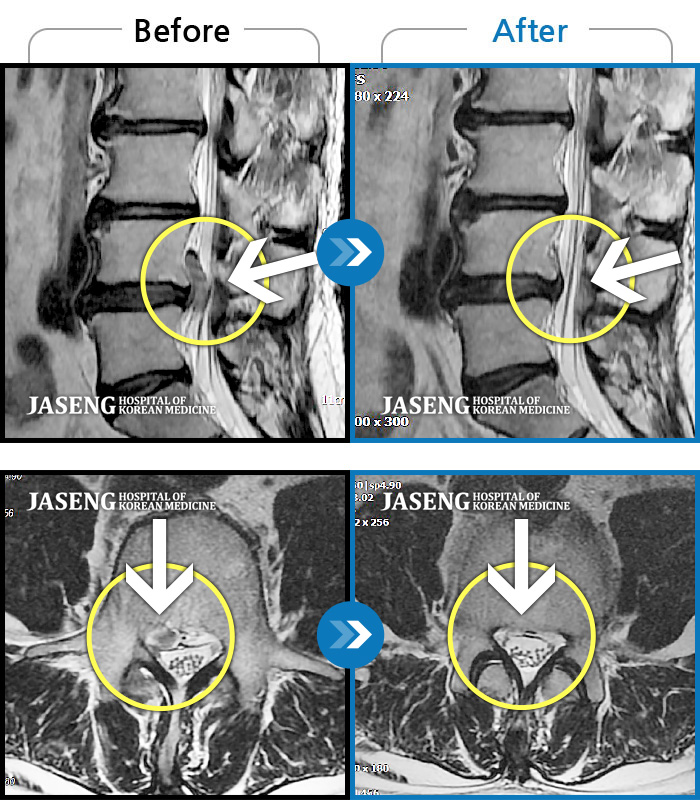

Before

After

환자에게 사전 동의를 받아 동일 조건에서 촬영되었습니다.

개인에 따라 치료 후 부작용이 발생할 수 있으니 의료진과 상담 후 치료를 진행하시기 바랍니다.

짐을 들면서 정리하다가 디스크가 터져서 내원, 후에 통증이 더 심해져 내원

허리와 엉치 부위 통증이 심해서 잠도 제대로 못자고 좋아하는 골프도 전혀 치지 못했어요.